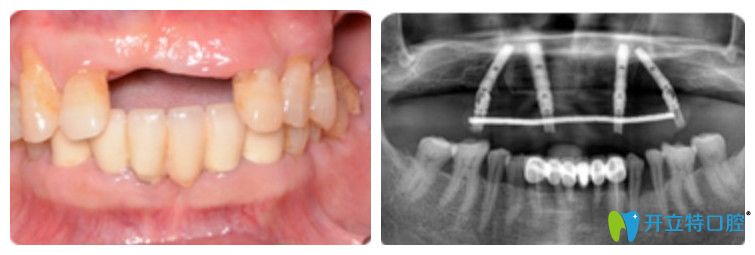

王先生在優(yōu)貝口腔做完種植牙前后圖

即刻用種植牙恢復(fù)半口好牙

王迪院長利用4顆種植體,兩顆種植體垂直植入牙槽骨內(nèi),另外兩顆采取傾斜角度植入牙槽骨內(nèi),然后在種植體的基臺安裝“拱形連橋”牙冠,實(shí)現(xiàn)半口牙種植。

王迪院長為王先生做的連橋牙冠

王先生半口牙種植前后的變化